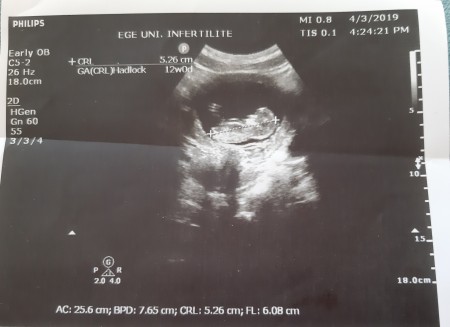

Down Sendromlu Bebek Ultrasonda Belli Olurmu

Down Sendromlu Bebek Ultrasonda Belli Olurmu.